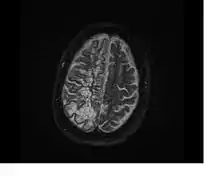

Axial fat-suppressed T2-weighted MRI image in the same patient as above demonstrating extensive dilated Type 2 perivascular spaces in the right hemisphere